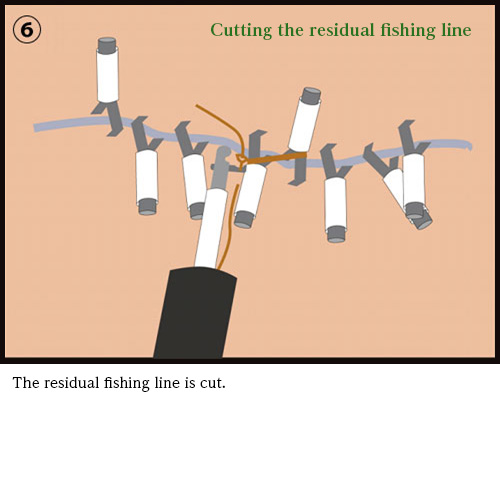

Dr. Mitooka has developed a novel and simple technique for the complete closure of large mucosal defects after ESD with hemoclips and fishing line using a conventional one-channel endoscope (up to 3cm in diameter for gastric specimens & 5cm in diameter for colonic specimens) allowing safer ESDs. ESD is a minimally invasive operation best suited for earliest stage of cancers and premalignant lesions, so that ESD in one day is possible. For those of you in need of ESD treatments and are busy, limited for time, or wish for a new treatment in one working day, please contact us.